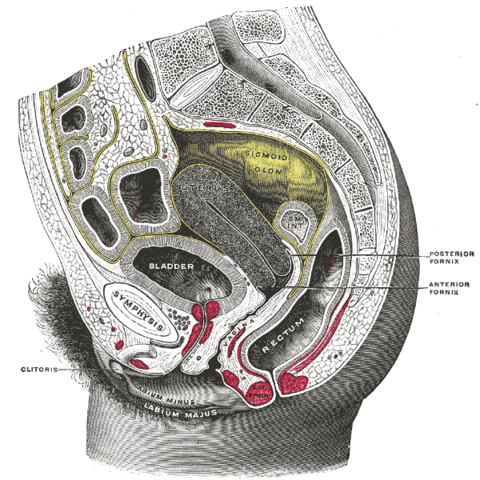

Arrangement of the Uterus, Ovary, and Uterine Tubes UterusOvaryTubes.gif

Gross Anatomical Location of the Uterus in the Pelvic Cavity UterusInPelvicCav.gif

Arrangement of the Uterus, Cervix, and Vagina UterusCervixVagina.gif